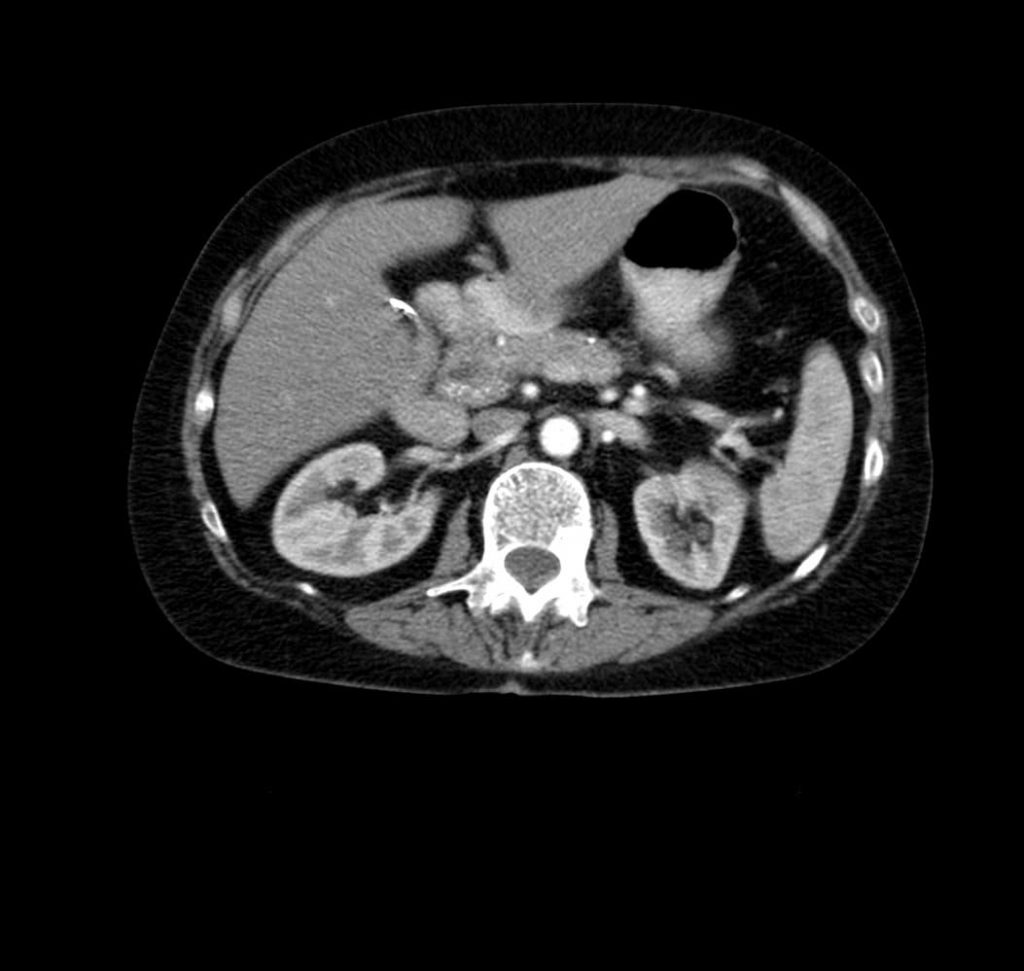

پانکراتیت حاد بیماری التهابی پانکراس است که غالباً به دنبال بیماری مجاری صفراوی یا سوءمصرف الکل ایجاد می شود. آسیب به پانکراس باعث ترشح موضعی آنزیمهای پروتئولیتیک گوارشی میشود که بافت پانکراس را در خود هضم میکند. پانکراتیت حاد معمولاً با درد اپیگاستر انتشار یابنده به پشت، تهوع، استفراغ و حساسیت اپیگاستریک هنگام لمس. تشخیص بر اساس تظاهرات بالینی، افزایش آنزیمهای پانکراسی سرم (آمیلاز، لیپاز) و یافتههای مربوط به تصویربرداری (CT ،MRI، سونوگرافی) داده میشود.